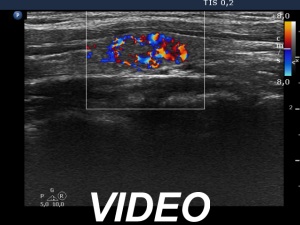

Second examination 3 years later (second row of images)

Clinical data: The patient had no complaints.

Palpation: unchanged.

Laboratory test: TSH 0.79 mIU/L.

Ultrasonography. Both the pattern and the size of the nodule in the right lobe remained unchanged. The cystic content of the left lobule has disappeared, it was replaced by inhomogeneous solid part. The vascularization of this lesion has also changed, the intranodular vascularization has become significantly increased.

Suggestion ultrasound in three years.

Comment. In the event of a cytological pattern which raises the suspicion of follicular tumor, we review the ultrasound records. By definition, a follicular tumor is surrounded with capsule. If none of the ultrasound signs of a capsule can be found, i.e. the nodule has neither halo nor perinodular blood flow than the risk of a follicular tumor is surely less than 5%. Be aware that more than 25% of cytologically suspected follicular tumors prove to be hyperplastic nodules on histopathology.